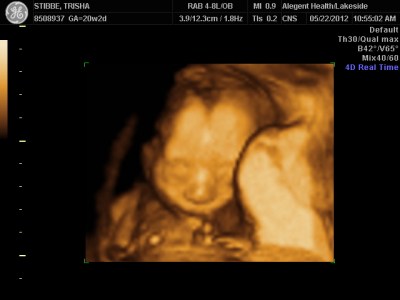

Ultrasound Day!